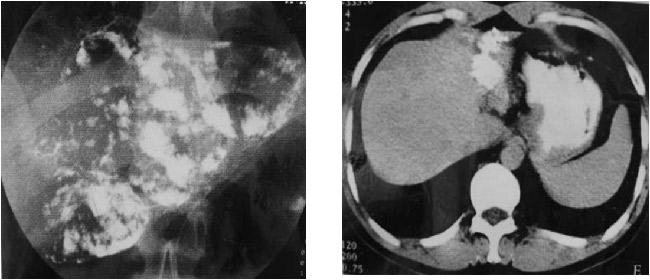

肝海绵状血管瘤为肝脏最常见的良性肿瘤,约占肝脏良性肿瘤的84%,好发于女性,发病率为男性的4.5-5倍。多见于30-60岁。肿瘤90%为单发,10%为多发。肿瘤直径从2mm到20cm...